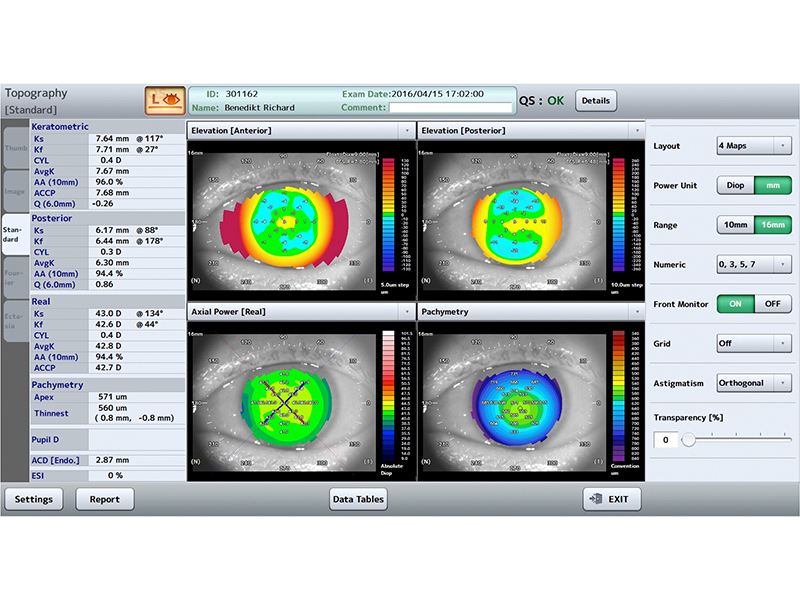

3D/2D анализ

Обзор в 3D

гониоскопия, срезы, вращения, ITC

Карты

Аксиальная сила (передняя, задняя, реальная), Сила рефракции (кератометрическая, передняя), Мгновенная сила (кератометрическая, переднаяя, задняя, реальная), Элевация (задняя, передняя), пахиметрия (карта, секторы), Эпителий, Глубина передней камеры, OCT (горизонтальная, вертикальная)

Функция анализа

Аксиальная сила (передняя, задняя, реальная), Сила рефракции (кератометрическая, передняя), Мгновенная сила (кератометрическая, переднаяя, задняя, реальная), Элевация (задняя, передняя), пахиметрия (карта, секторы), Эпителий, Глубина передней камеры, OCT (горизонтальная, вертикальная)

Экспорт видео

Просмотр в режиме 2D вращением/С-скан -3D виде